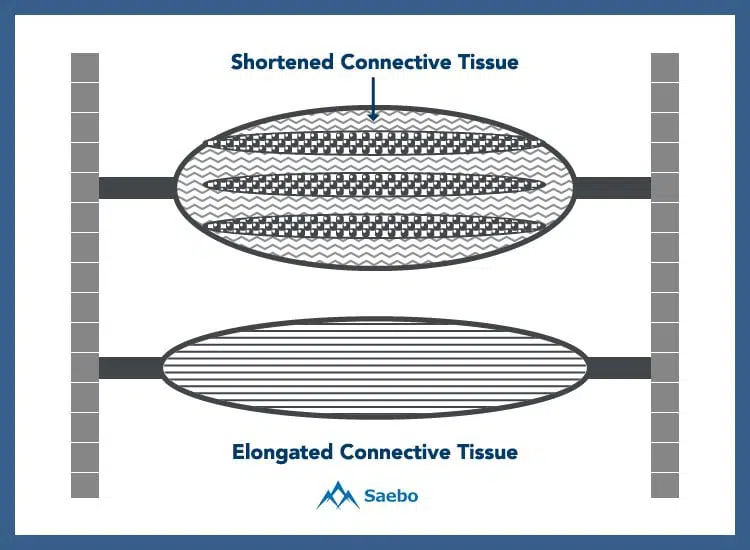

Contracture causes the muscles in the hand and wrist to tighten and shrink, which often causes rigidity and deformity of the joints. Besides strokes, other common causes of contracture include burns, cerebral palsy, muscular dystrophies, and adrenoleukodystrophy.

Soft tissue that has been shortened due to contracture can be lengthened over time with dedicated stretching and range-of-motion techniques.It’s recommended that the patients perform a low-load, prolonged stretch for 6 to 12 hours daily which is attainable by using a proper dynamic orthosis. The more the affected limb practices functional use, the better the results will be. There are many techniques that can be implemented to increase mobility throughout the joint. These include passive stretching, manual therapy, serial casting, assistive devices, orthoses, electrotherapeutic modalities, or surgery.